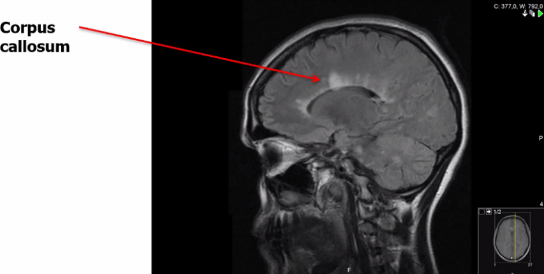

Klassiska lokaler vid MS på en MR-bild?

A

• Nära ventriklar

• Kring corpus callosum (massa axoner som går över hjärnbalken)

• Juxtakortikalt (nära kortex)